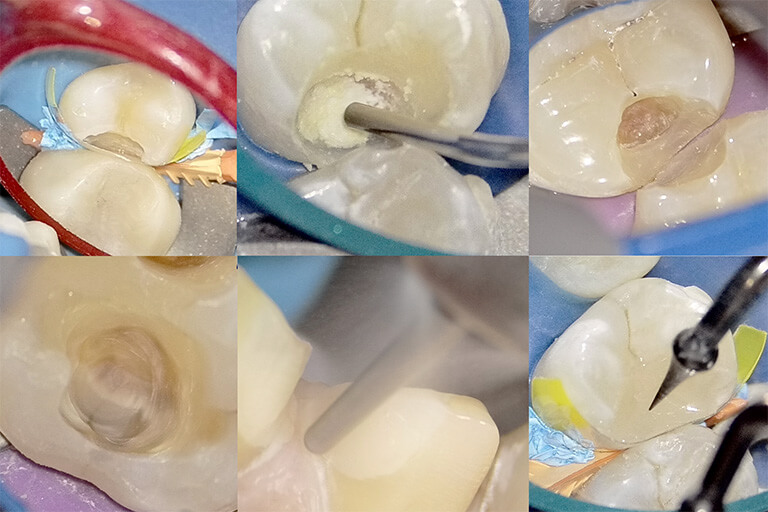

5. NK dental TOKYOが提案する『早めの処置』と『MI治療』

脅かすようなことばかり書いてしまいましたが、安心してください。 『ヒビは、早めに見つけて適切に処置をすれば、トラブルを最小限に抑えることができます』。

当院が大切にしているのは、『MI(Minimal Intervention:最小侵襲治療)』、つまり「できるだけ歯を削らない」という考え方です。

削る量を少なくするための早期発見

ヒビが浅いうち(エナメル質にとどまっている段階、あるいは象牙質のごく浅い部分)であれば、大きく削る必要はありません。

『マイクロスコープによる確定診断』 まず、どこに、どの程度の深さのヒビが入っているかを正確に見極めます。

『接着修復(ボンディング)』 ヒビの部分をわずかに整理し、流動性の高い高性能な接着材(レジン)を流し込みます。これにより、ヒビを物理的に『封鎖』し、細菌の侵入経路を断ちます。同時に、ヒビがこれ以上広がらないように補強する効果もあります。

『クラウン(被せ物)による保護』 すでにヒビが深く、噛むたびに歯がたわんで痛むような場合は、歯全体を覆う被せ物(クラウン)を選択することもあります。これにより、歯が割れる方向への力がかかるのを防ぎ、「タガをはめる」ように歯を守ります。

「痛くなってから」ではなく「ヒビがある段階で」処置をすることで、神経を残せる確率は格段に上がりますし、ご自身の歯の寿命を延ばすことに直結します。